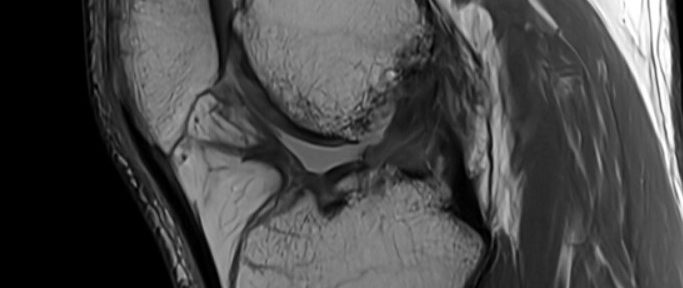

〖自然治癒症例43〗ギリシャ人・50歳女性:前十字靭帯完全断裂が手術なしで良好に自然修復

【自然治癒症例42】スキー中に断裂した膝の前十字靭帯…彼女が選んだのは“手術しない”選択肢